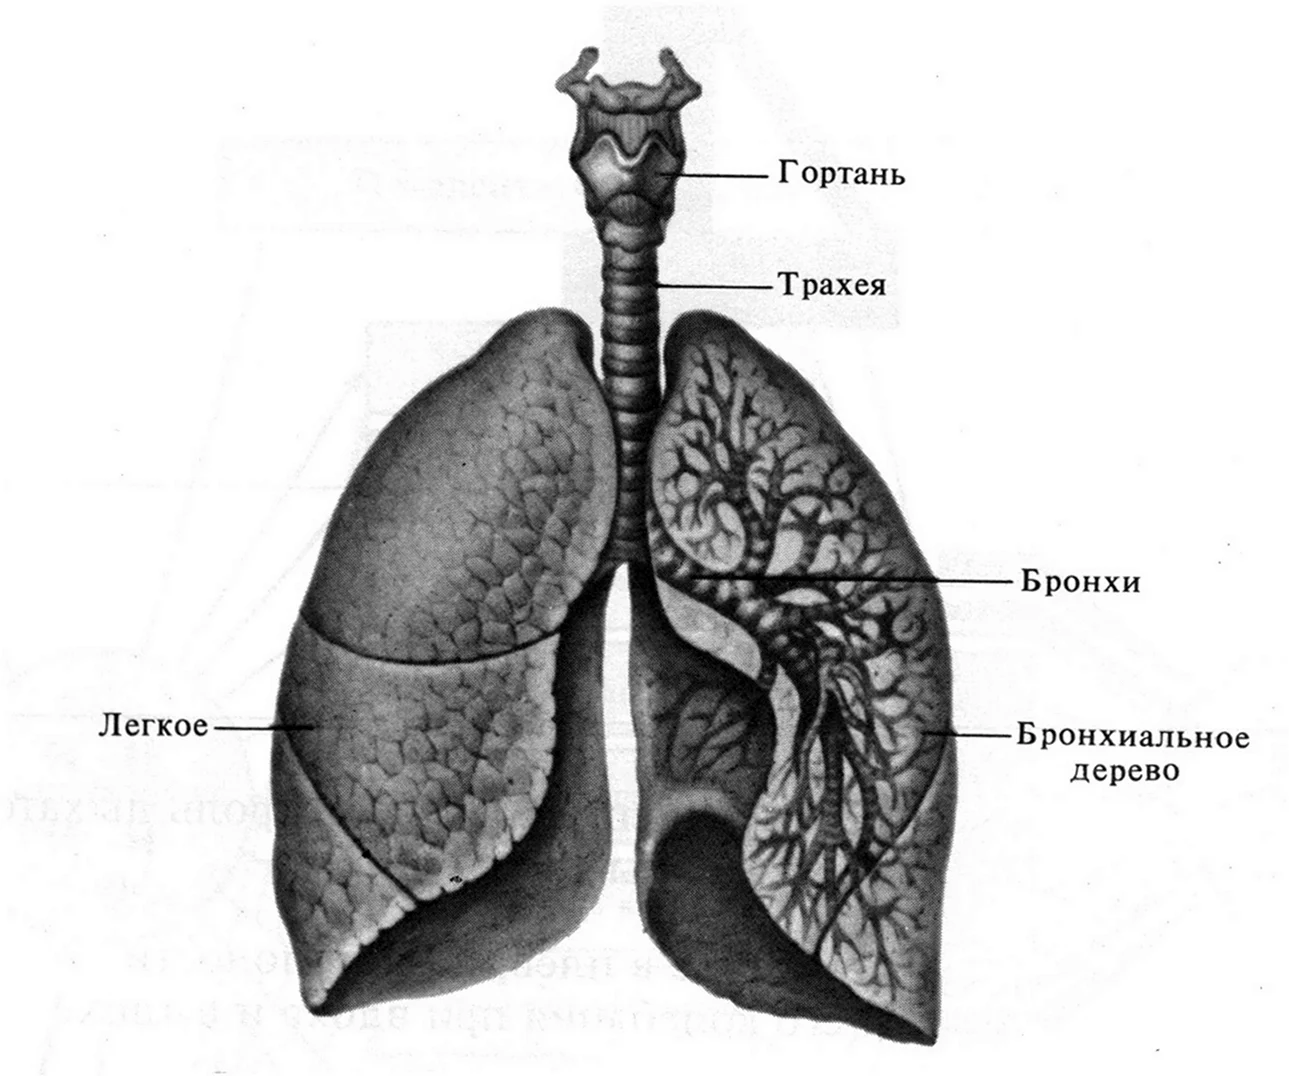

Здоровье дыхательной системы: бронхи и легкие